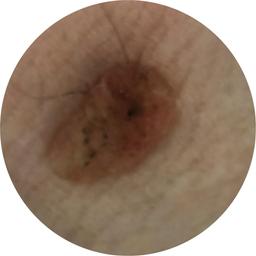

anatom_site_1 Upper extremity

anatom_site_general upper extremity

diagnosis_1 Benign

diagnosis_confirm_type single image expert consensus

image_type dermoscopic